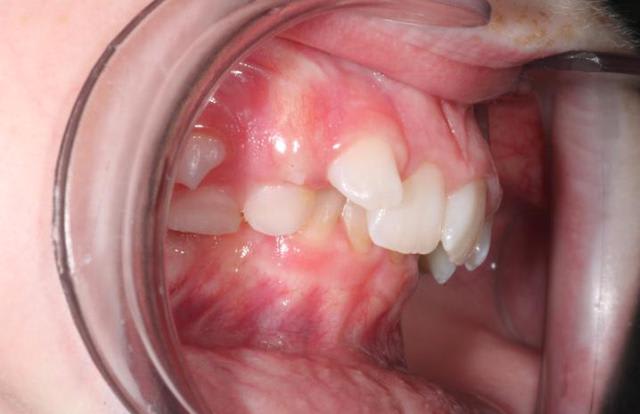

Petite patiente, 9 ans et demi.

j'avais essayé deux mois un bihélix mandibulaire il y a deux ans. Echec complet.

Je la revois aujourd'hui. Evidement, cela ne s'est pas arrangé.

J'avoue etre en panne d'option thérapeutique, a part la disjonction médiane au piezo. Des plaques à pistes ?

D'autres idées ? si chirurgie, vers quel age ?

Syndrome de Brodie?

Unilatéral à droite? (on ne voit pas bien à gauche).

C'est comment en RC? Est-ce que le verrouillage antérieur provoque une rétropulsion ou alors il y a vraiment une brachymandibulie?

si c'est une brachymandibulie, tu peux lui poser une plaque avec un vérin mandibulaire mais assure-toi qu'il ne s'agit pas d'une version alvéolaire aggravée par le scissor-bite

l'analyse de Delaire sur une téléradio de face te donnera la confirmation d'une micromandibulie vraie ou pas

Sans la radio de face je pense que c'est difficile d'opter d'emblée pour la distraction chir. Surtout si c'est unilatéral. En plus j'ai l'impression que tu as une belle version corono linguale à droite.